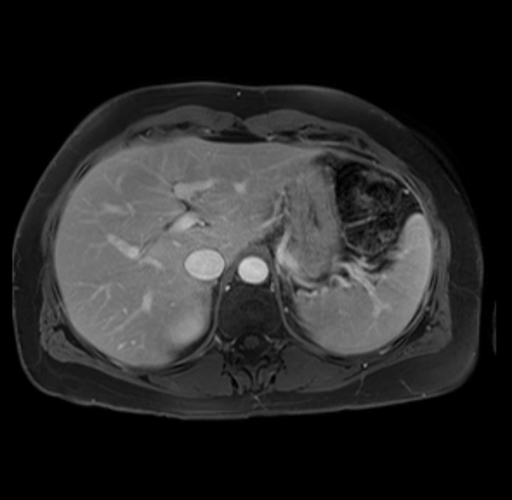

Imaging Analysis

Look through the patient's CT scan to identify any areas of concern for the necessary procedure.

Based on your CT findings, which issue(s) are present and would give reason for "planned slowing down moment(s)" in this case?